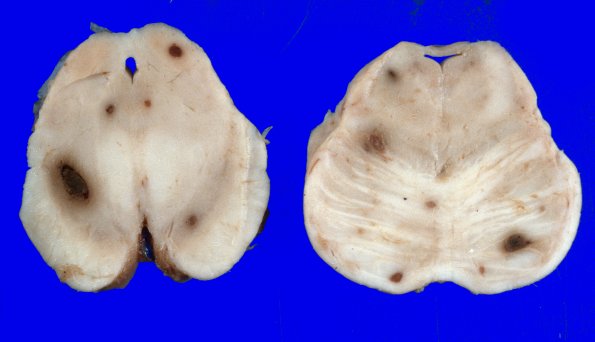

1C1 Leukemic nodules (Case 1) gross 1

The brainstem in this case shows similar, although smaller, leukemic nodules. (H&E)